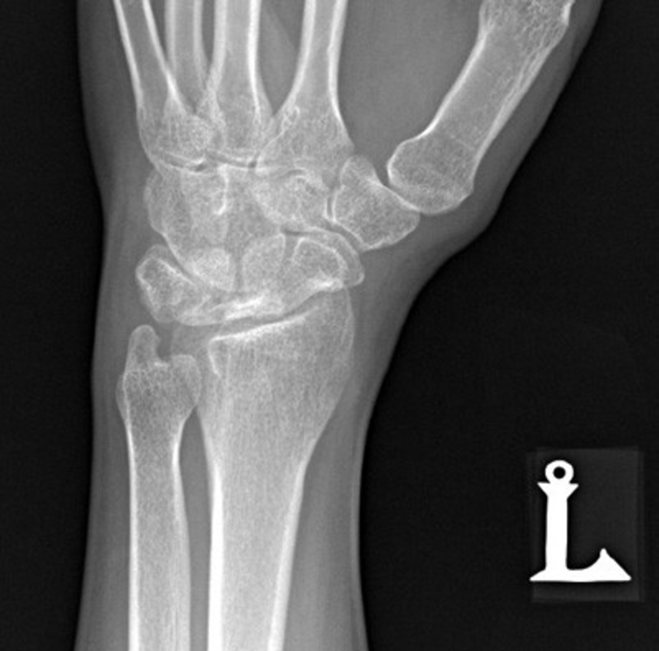

What view is this?

clenched fist view

What’s another name for clenched fist view

stress view PA

What is the clenched fist view used for

identify scapho-lunate dissociations

What does this image show

gap between the scaphoid and lunate